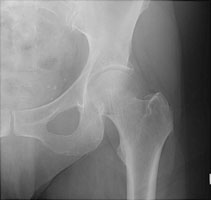

Femoral neck fractures also result from falls, especially in elderly and osteoporotic females. They are associated with radial and humeral fractures. The Garden classification is widely used to categorize these fractures. Garden I is an incomplete fracture through the femoral neck while with Garden II, the fracture is complete. With Garden III fractures, there is impaction, and with Garden IV, the femoral neck is superiorly migrated relative to the femoral head. Garden IV fractures have the highest risk of avascular necrosis.

A | AP view reveals a Garden II fracture of the left hip. |